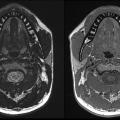

Update zu bildgebenden Verfahren in der Zahnmedizin: Aufnahmen zu Magnetom Free.Max dental edition (ddMRI)